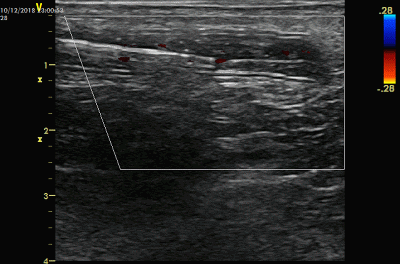

然后经导管内脉冲式注射溶栓药液。如下图。脉冲式注射的目的是希望喷射的药液有一定冲击力,对血栓有机械碎裂作用,这种作用在使用多侧孔溶栓导管更为明显。

一边缓慢回撤导管,一步注射,直到鞘管部位。可以使用彩色多普勒观察药液喷射的信号。